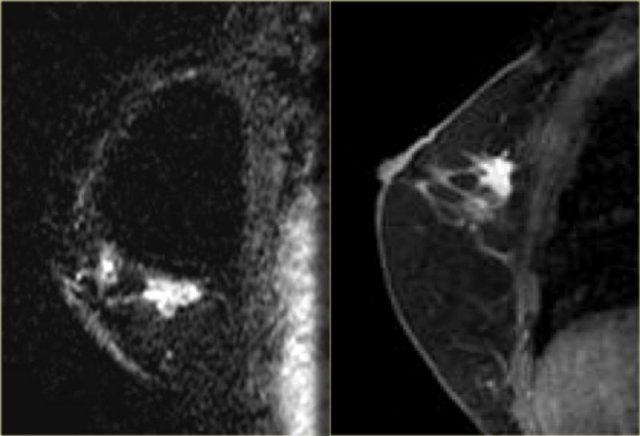

Invasive ductal carcinoma

Most invasive carcinoma are ductal, some are lobular, and there is a group of rarer types.

Regardless of the type of cancer, they typically appear on breast MRI as an irregularly shaped,

spiculated mass with rim- or heterogeneous enhancement after the administration of intravenous gadolinium.

On the left two cases.

The image on the far left is an invasive ductal carcinoma presenting as a large, heterogeneously enhancing mass.

Next to it an example of an invasive ductal carcinoma presenting as a smaller mass with rim-enhancement.

The image on the far left shows an irregular mass with some ductal extension, and

on the right an irregular mass extending to the chest wall, but not invading it.

There is no chest wall enhancement.